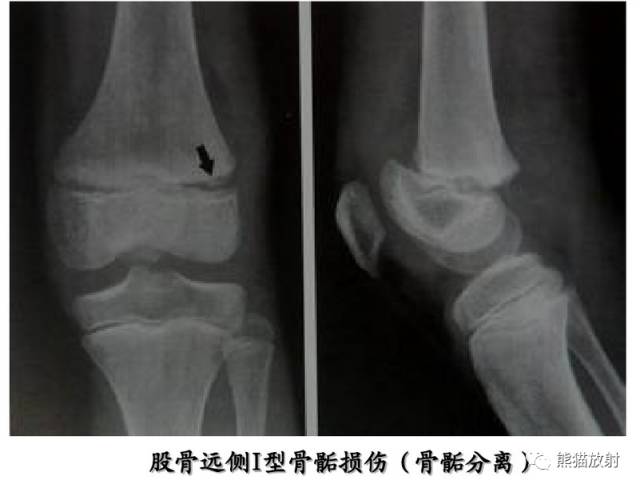

Salter-Harris I型:干骺端及骨骺分离

平片通常为正常,可表现为骺板增宽或骨骺轻度移位。

第一型(Ⅰ型) 骨骺分离,分离一般发生在生长板的肥大层,故软骨的生长带留在骨骺一侧,所以多不引起生长障碍;婴幼儿骺板软骨层较宽,容易发生骨骺分离,据统计,占骨骺损伤的15.9%;唯一的x线征象是骨化中心移位,该型复位容易,预后良好;而股骨头骨骺分离由于骨骺动脉多被破坏,预后不佳。该型也可见于坏血病、佝偻病、骨髓炎和内分泌疾病所致的病理性损伤。